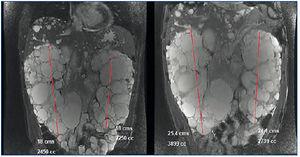

En marzo de 2011 inicia tratamiento con adalimumab (Humira®) 40 mg cada 15 días. En ese momento presenta: hemoglobina (Hb) 12,4 g/dl, creatinina (Cr) 2,3 mg/dl, filtrado glomerular estimado (FGe) MDRD (Modification of Diet in Renal Disease) 34 ml/min/1,73 m2, proteinuria de 10 mg/dl. En septiembre de 2011 muestra: Cr 3,24 mg/dl, FGe MDRD 23 ml/min/1,73 m2, proteinuria 1,78 g/24 h (figura 1). Se suspende el tratamiento en enero de 2012 por el desarrollo de polineuropatía y púrpura. En febrero de 2012 una resonancia magnética nuclear (RMN) demuestra riñón derecho de 18 cm (volumen de 2450 ml) y riñón izquierdo de 18 cm (2250 ml). En abril de 2012 se inicia Golimumab (Simponi®) 50 mg cada cinco semanas. Se administran seis dosis y se suspende en septiembre de 2012, al referir el paciente un llamativo aumento del diámetro abdominal y hernia umbilical que se relaciona directamente con la administración del fármaco. En diciembre de 2012 se administra una última dosis. En marzo de 2013, una nueva RMN demuestra riñón derecho de 25,4 cm con un volumen de 3899 ml y riñón izquierdo de 24,1 cm con un volumen de 2739 ml (figura 2) y discreto aumento en mucha menor cuantía de los quistes hepáticos.

Figura 2. Imagen comparativa del tamaño renal en las resonancias magnéticas nucleares de 2012 (izquierda) y 2013 (derecha).